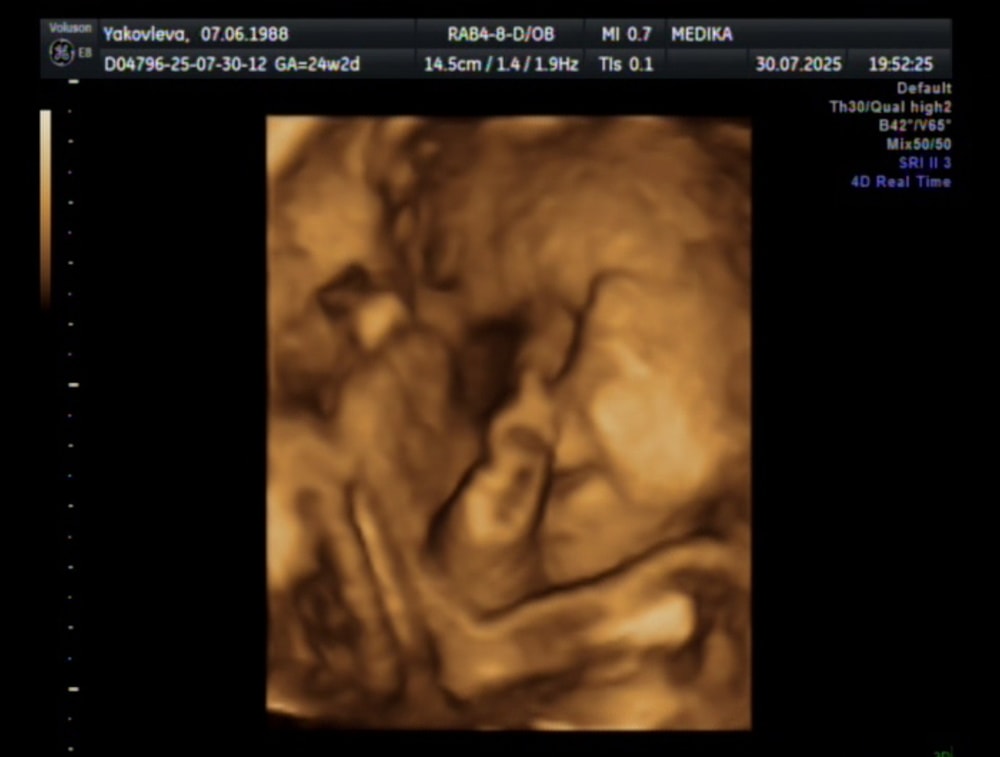

Сделали 3Д УЗИ

Сходили с мужем посмотрели на сыночка🥰

Растем и развиваемся по сроку

А щечки то миленькие 🤗